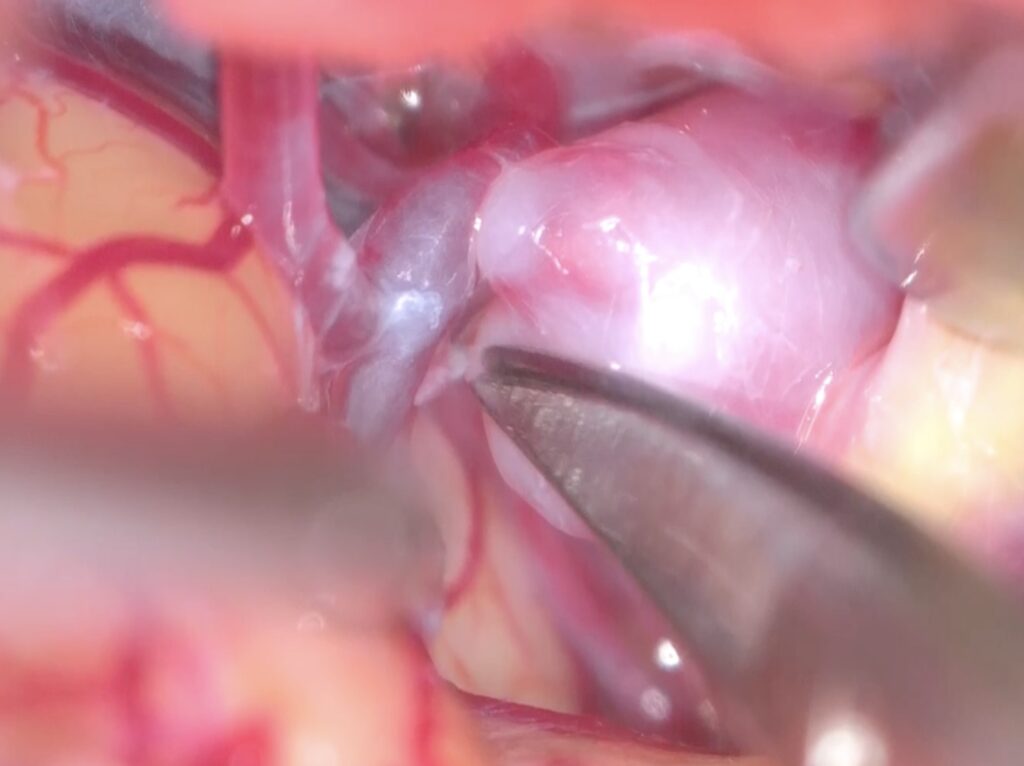

硬膜切開を行い、シルビウス裂を開けると動脈瘤が容易に露出されました。

動脈瘤に張り付いた小動脈をsharp dissectionにより剥がしネックを露出しました。